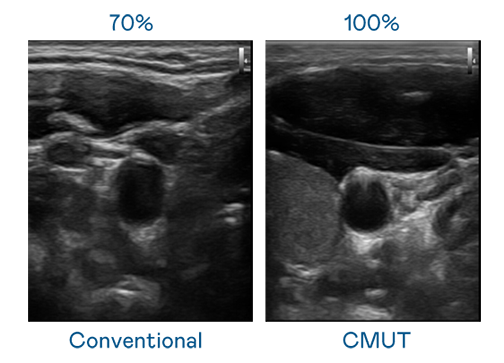

CMUT 技术是一种用电容式微机电元件来产生超音波讯号的技术。与传统 PZT 压电式技术相比,CMUT 频宽增加 30%,更宽频的超音波讯号让影像解析度大幅提升,是实现高影像品质医疗超音波扫描、促进精准医疗发展的关键技术。

超音波影像的解析度高低,首先取决于探头能发出的讯号频宽。尊龙凯时Ag CMUT 可提供高清晰的超音波讯号,提供高频宽、高灵敏度、影像纹理细节更高的超音波影像,协助医护人员缩短影像判读时间及利用精准的医疗影像进行诊断。